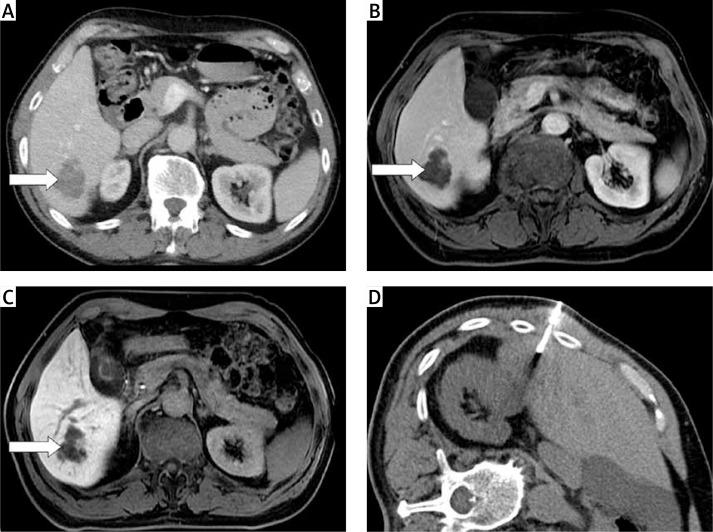

Is percutaneous computed tomography-guided biopsy sufficient to establish indolent lymphoma transformation?

The aim of the study was to retrospectively evaluate the technical features, efficacy, accuracy, and relevant complications of computed tomography-guided biopsies in various anatomical localizations when diagnosing indolent lymphoma transformations, relapses, duplicate malignant diseases or benign processes.

From December 2007 to December 2017, 81 percutaneous biopsy procedures in 72 patients for tumors, sizes 17-232 mm in diameter (median length: 39 mm), were performed in patients with known indolent lymphomas in their clinical history. The patients were men in 41 cases and women in 31 cases, aged 36 to 86 years.

In 79 cases (97.5%; 95% CI: 91.3-99.7) results were true positive or true negative; only 2 interventions (2.5%; 95% CI: 0.3-8.6) were histologically false negative. Transformation was verified in 29 cases (35.8%; 95% CI: 25.4-47.2), relapses in 30 cases (37%; 95% CI: 26.6-48.5), duplicate malignancy in 15 cases (18.5%; 95% CI: 10.8-28.7) and benign processes in 7 cases (8.7%; 95% CI: 3.5-17.0). Eight complications in total were revealed, 7 of which were in consequence of thoracic cavity biopsy. A statistically significant relationship between the complication incidence and anatomical localization in the thoracic cavity was identified ( = 0.0104).

Percutaneous CT guided biopsy performed in patients with a history of indolent lymphoma had high accuracy in establishing the correct diagnosis regarding transformation, relapse, duplicate malignancy or a benign process. Simultaneously, the complication rate was low.